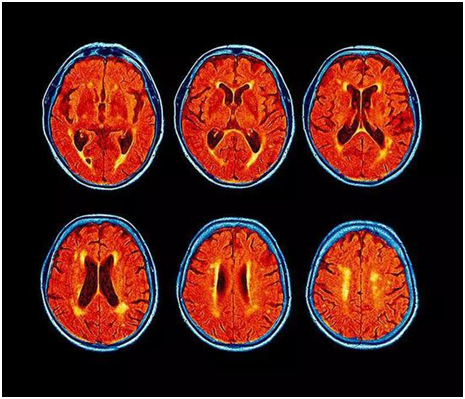

兒童的血腦屏障更容易被穿越,因此科學家們對兒童受到的影響感到愈加擔憂。一些研究人員開始使用核磁共振掃描分析這些污染物對神經發育造成的影響,結果顯示,大腦中的確發生了一些變化。

研究人員分析了145名12歲兒童的大腦核磁共振掃描結果,并利用住址信息估測他們接觸到的污染程度,包括細顆粒物等,在分析中還考慮了人口統計學因素,確保社會經濟狀況和種族等因素與這些影響無關。

在比較了這些兒童近期接觸的交通空氣污染水平、焦慮癥狀、以及大腦成像信息后,該團隊發現,污染暴露程度較高的兒童所報告的一般焦慮癥狀也更多,而在這些癥狀更嚴重的兒童大腦中,負責情緒處理的前扣帶皮層中的肌醇含量較高,正常大腦中也含有肌醇,但肌醇水平異常往往與大腦病變有關。